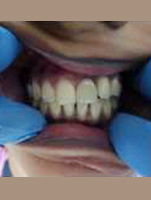

After Placement of Prosthesis

Single Tooth Implant

Post Operation